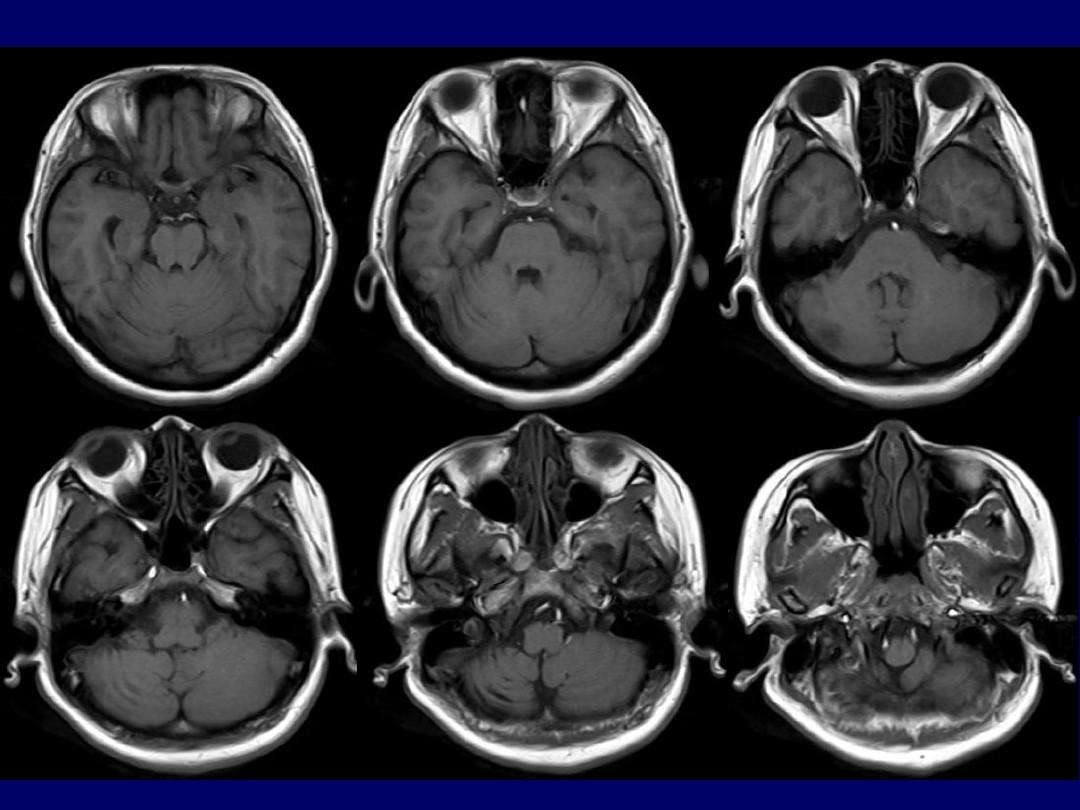

梅元武等:中枢神经系统感染

图片尺寸640x481